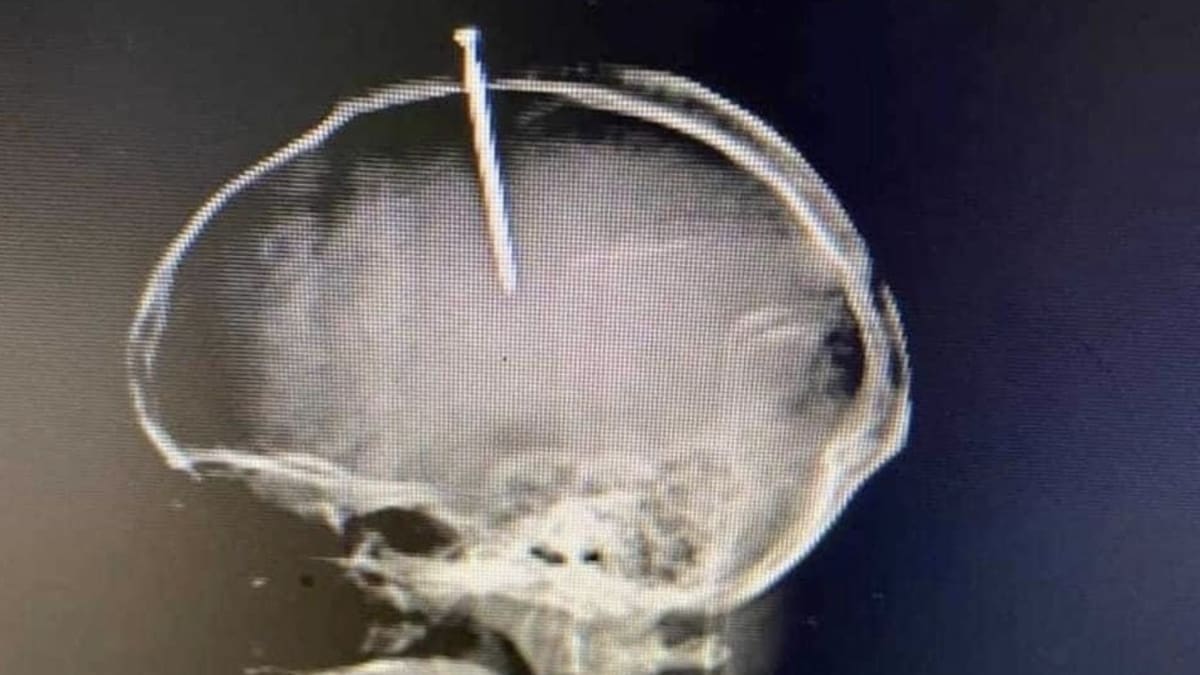

'Se sentía el cerebro flojo', estas fueron las declaraciones que hizo Natanael García Polanco, de 33 años, a los médicos que lo atendieron en el Hospital José María Cabral y Báez, en República Dominicana, tras incrustarse un clavo en la cabeza.

En un reporte entregado por la jefa de servicios de Neurología del hospital, informaron que intervinieron quirúrgicamente para extraer los elementos, lo cual se logró con éxito y no se produjo ninguna lesión importante.